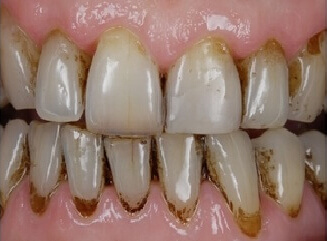

Probleem. Hambakivi on nähtav hambapindadel.

Lahendus. Protseduuri käigus eemaldatakse hambapindadelt hambaplaak, kasutades ultraheli-skaalerit ja tahmapuhurit (“Air Flow”). Protseduuri lõpus hambad poleeritakse.